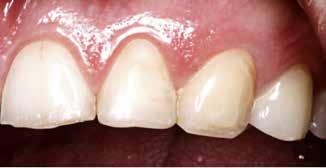

PATIENTTILFÆLDET

En 40 år gammel mand henvendte sig med bekymring for både æstetik og symptomer fra tænderne (Fig. 1). Han fortalte, at

Præoperativ status

Fig. 1. 40-årig sund og rask mand møder bekymret for sine slidte tænder. Klinisk ses frakturer og substanstab langs incisalkanterne på overkæbetænderne.

Fig. 1. A 40-year-old healthy man is concerned for his worn teeth. Clinically, fractures and loss of tooth substance are observed at the incisal edge of the upper front teeth.

Klinisk undersøgelse viste et tandsæt med enkelte restaureringer, men med slitagedefekter okklusalt/incisalt på samtlige tænder fra 6’er til 6’er i over- og underkæbe (Fig. 2). Defekterne strakte sig tydeligt ind i dentinen. Baseret på anamnesen og de kliniske fund blev erosion set som hovedårsagen til tandsliddet, mens attrition formodedes at være en medvirkende faktor.

Postoperativ status

okklusal-vertikale dimension. De afficerede dentinoverflader blev ridset i overfladen med en grov diamant, men derudover blev der ikke foretaget nogen form for kavitetspræparation, da intentionen var at gennemføre en minimalt invasiv behandlingstilgang. Kofferdam blev anlagt i hvert arbejdsfelt (Fig. 3) og adhæsivet påført med en æts-og-skyl-strategi (ætsning af emalje og dentin, primer, adhæsiv). Derefter blev tænderne bygget op med en mikrohybrid komposit for at genskabe tandens naturlige form (Fig. 4). I underkæbefronten blev der kun lagt et tyndt lag med komposit pga. pladsmangel. Efter omhyggelig pudsning og polering havde patienten okklusion på samtlige tænder og var tilfreds med både funktion og æstetik.

Fig. 4. Færdigrestaurerede tænder med komposit.

Fig. 4. Final restored teeth with composite.